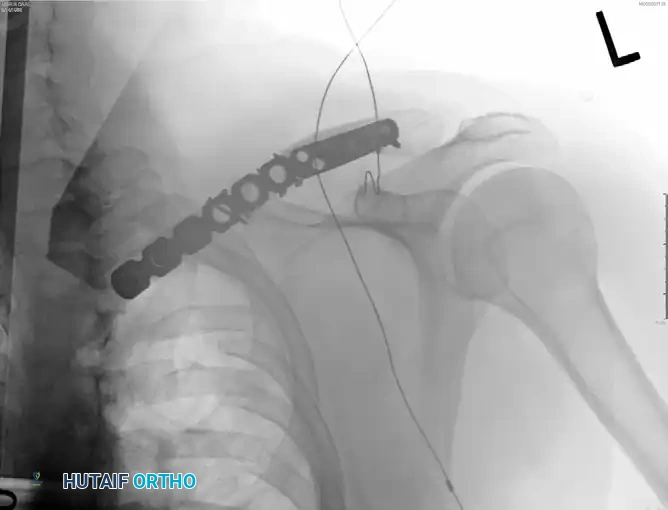

Figure: Postoperative radiograph demonstrating anatomic reduction and fixation with a superiorly placed precontoured plate.

Figure: Postoperative radiograph demonstrating fixation with an anteroinferior plate.

* Plate Application: Apply the precontoured superior plate. Ensure the plate spans the fracture adequately, aiming for at least three (preferably four) bicortical screws in both the medial and lateral main fragments.

Figure: Screw placement must be directed posteriorly and slightly superiorly to avoid plunging into the neurovascular bundle.